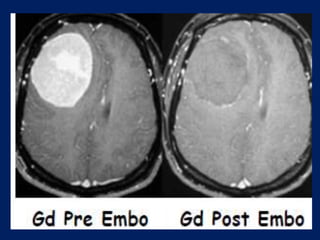

hypervascular, receiving their blood supply predominantly from

dural vessels.